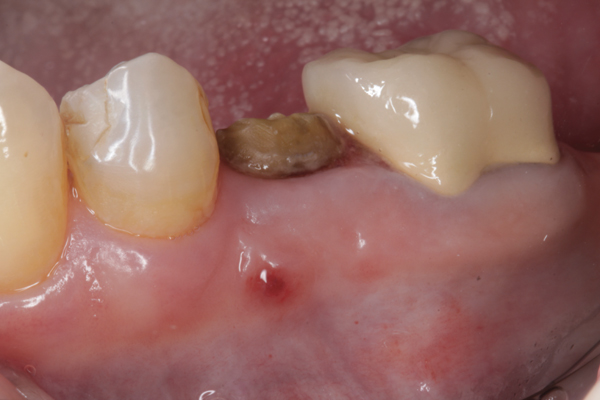

Fig 1. (Case 1) Tooth No. 19 manifested a buccal fistulous tract. Probing depth on the buccal was 8 mm.

Figure 1